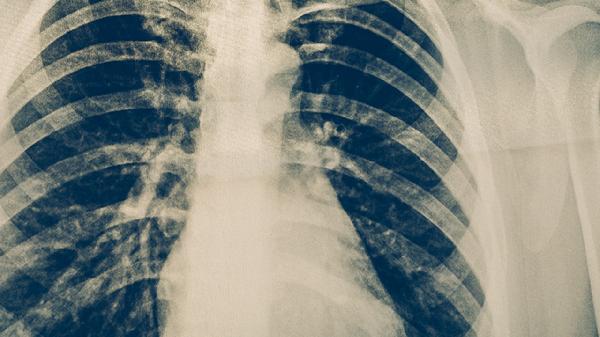

肺梗阻的诊断主要依靠影像学检查,如CT肺动脉造影、核素肺通气灌注扫描和超声心动图。血液检查如D-二聚体水平升高也有助于诊断。早期诊断对改善预后至关重要,任何疑似症状都应尽快进行相关检查。